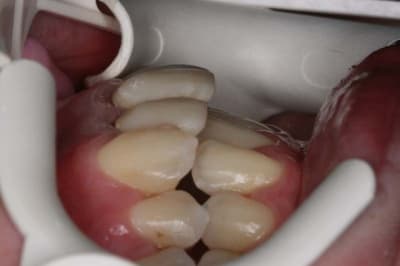

Voici le cas il y a 8 jours, c.a.d. 1 an et 1 mois après les photos de son dernier rendez vous

entre temps, elle est allée se faire faire des provisoires sur 12/11 par un confrère plus prés de son domicile

voici le résultat de l’absence de contention, qui aurait été (a mon avis) une erreur compte tenu que le cas n’était pas terminé

c’est mal foutu, c’est déglingué mais je n’ai aucune malposition Inc. Inf.

c.a.d. : AUCUNE RECIDIVE D’ENCOMBREMENT AVEC ROTATIONS

les dents ne sont pas alignées, mais j’ai mon espace globale, je peux poursuivre ce traitement avec sérénité